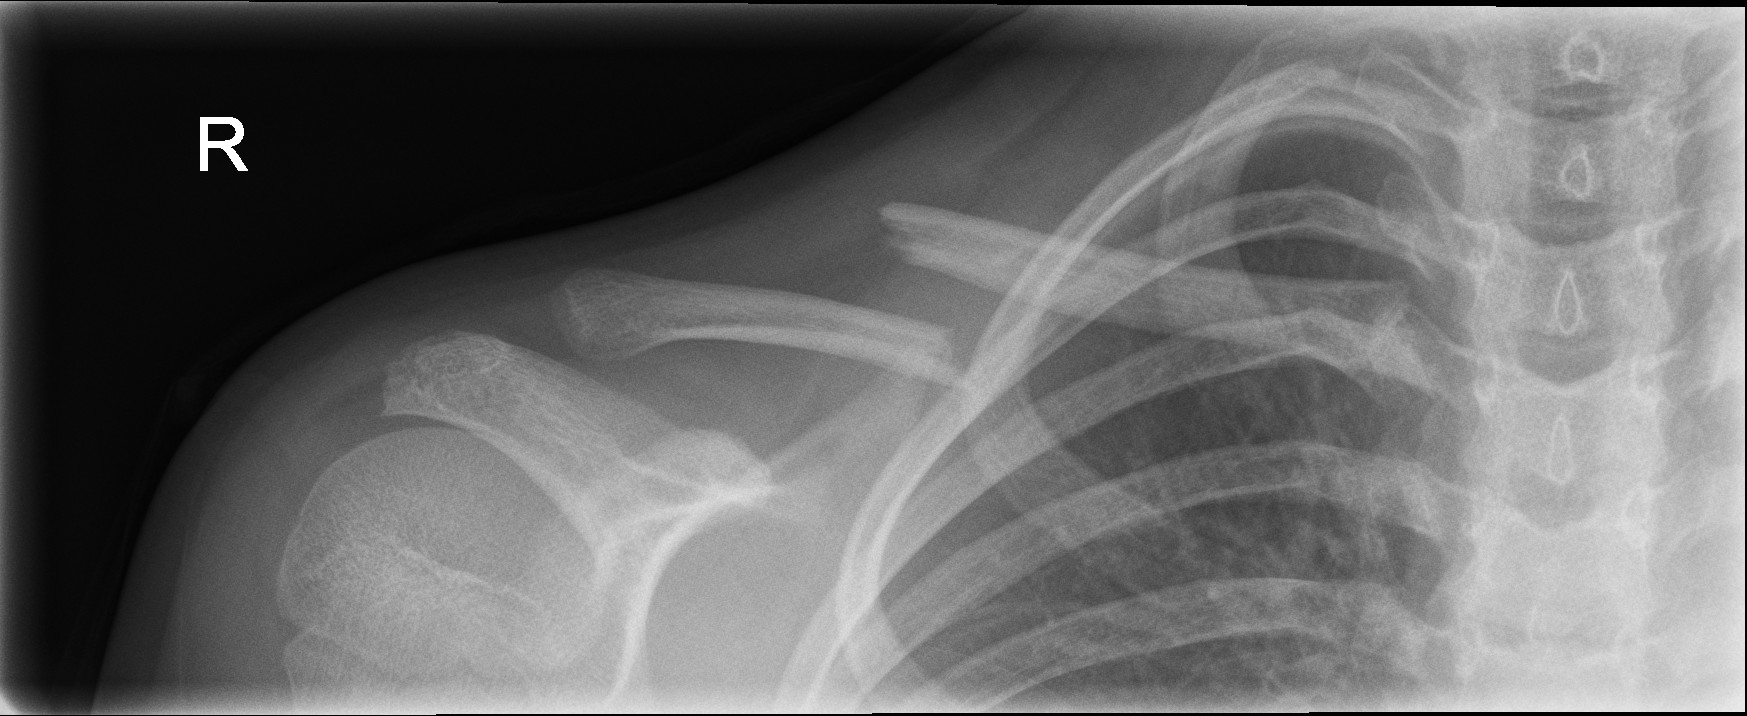

Minimally displaced middle third clavicle fracture

Significantly displaced middle third fractures